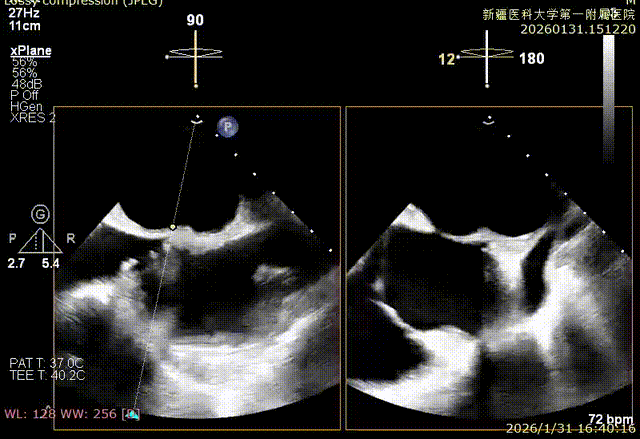

XPLAN切面2区后叶栓系

XPLAN切面中重度反流

XPLAN后叶严重栓系

Bicom切面中重度反流